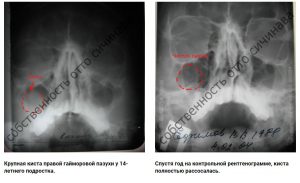

Первый зафиксированный случай рассасывания кист и полипов носа, в истории медицины, принадлежит нашей клиники!

Впервые в истории медицины киста и полипы рассосались в Москве в нашей клинике.